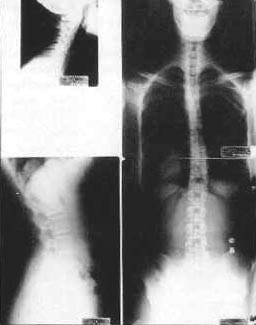

Spinal X-rays may be taken depending on your age, and situation. There are many reasons why we would not take x-rays on certain patients including pregnancy, most children, recent usable spinal x-rays and some other various situations. Aside from these situations, x-rays are a common part of the examination process when looking for vertebral Subluxation. X-rays give us important information including the position of the spinal bones, and the quality of the spine and safety of adjusting it. X-rays also tell us the relative length of time Subluxation may have been involved in your spine.

With this important information we can make a more accurate determination of the type of adjustments your spine needs as well as the initial frequency of your care. Your x-rays we be explained to you and covered in detail at your Report of Findings.